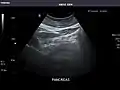

Gallbladder

Gallbladder: No stones, wall thickening, or pericholecystic fluid.

Common Bile Duct: Nondilated measuring 1.3 mm at the level of the porta hepatis.